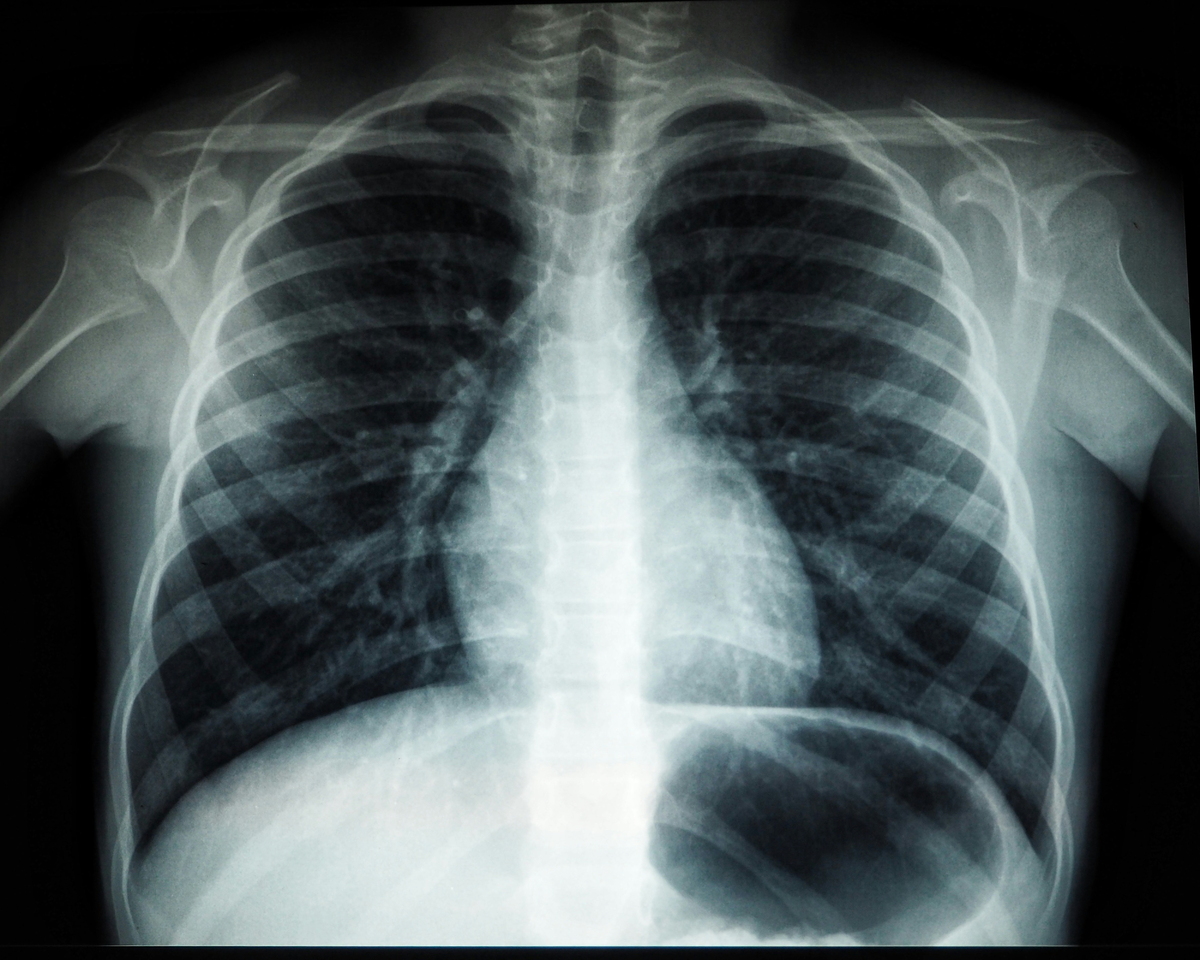

세계보건기구(WHO) 자료에 따르면 흉부 엑스레이 1회 촬영 시 노출되는 방사선량은 약 0.02~0.1mSv다. 치과 엑스레이는 0.005~0.01mSv, 복부 CT는 5~10mSv 수준이다.

흉부 엑스레이 한 번은 일상에서 며칠간 자연 상태로 노출되는 방사선량과 비슷한 범위로 알려져 있다. 단일 촬영의 위험 자체는 매우 낮은 편이다.

저선량 노출의 영향은 피폭량이 누적될수록 암 발생 위험이 통계적으로 소폭 증가할 가능성이 있다는 ‘확률적 영향’으로 분류된다. 엑스레이 자체가 문제가 되기보다는 통제되지 않은 반복과 누적이 관리의 핵심이다.

서울의 한 대형병원 영상의학과 교수는 “흉부 엑스레이 1회의 선량은 장거리 항공편에서 받는 우주 방사선량과 비슷하거나 낮은 수준”이라며 “막연한 공포로 꼭 필요한 진단 검사를 피하는 것이 오히려 더 큰 위험이 될 수 있다”고 말했다.